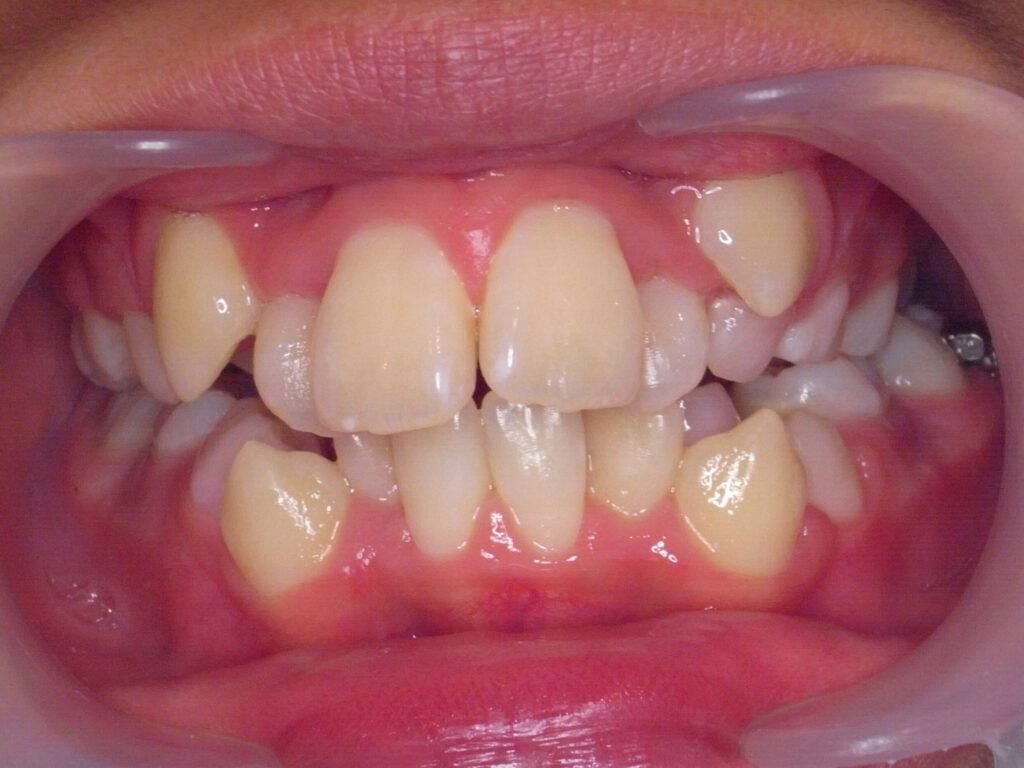

BEFORE:2016年